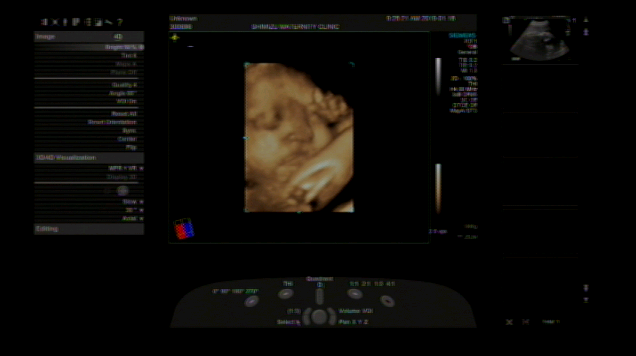

32週6日(32w6d・男の子)|みい(^-^) さん(25歳)

エコー写真撮影時のエピソード:

なかなかお顔を見せてくれず、やっと見えたお顔は頬杖をついた不機嫌?!な表情で、思わず笑ってしまったのを覚えています。産まれてからも色んな表情を見せてくれる我が子の成長をこれからも見守っていきたいです。